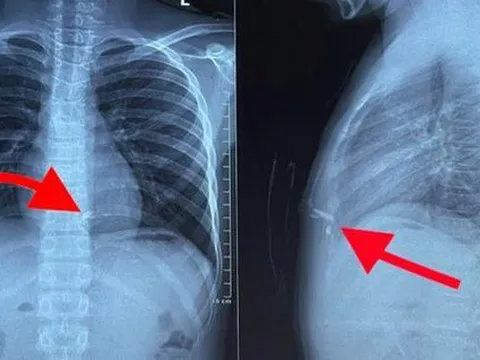

Chiều 27/1, ông Lê Hồng Việt, Chủ tịch UBND xã Xuân Vân (H.Yên Sơn, Tuyên Quang), cho biết trên địa bàn vừa xảy ra vụ nổ nghi từ pháo tự chế khiến 4 học sinh cấp 1 bị thương, phải nhập viện cấp cứu.